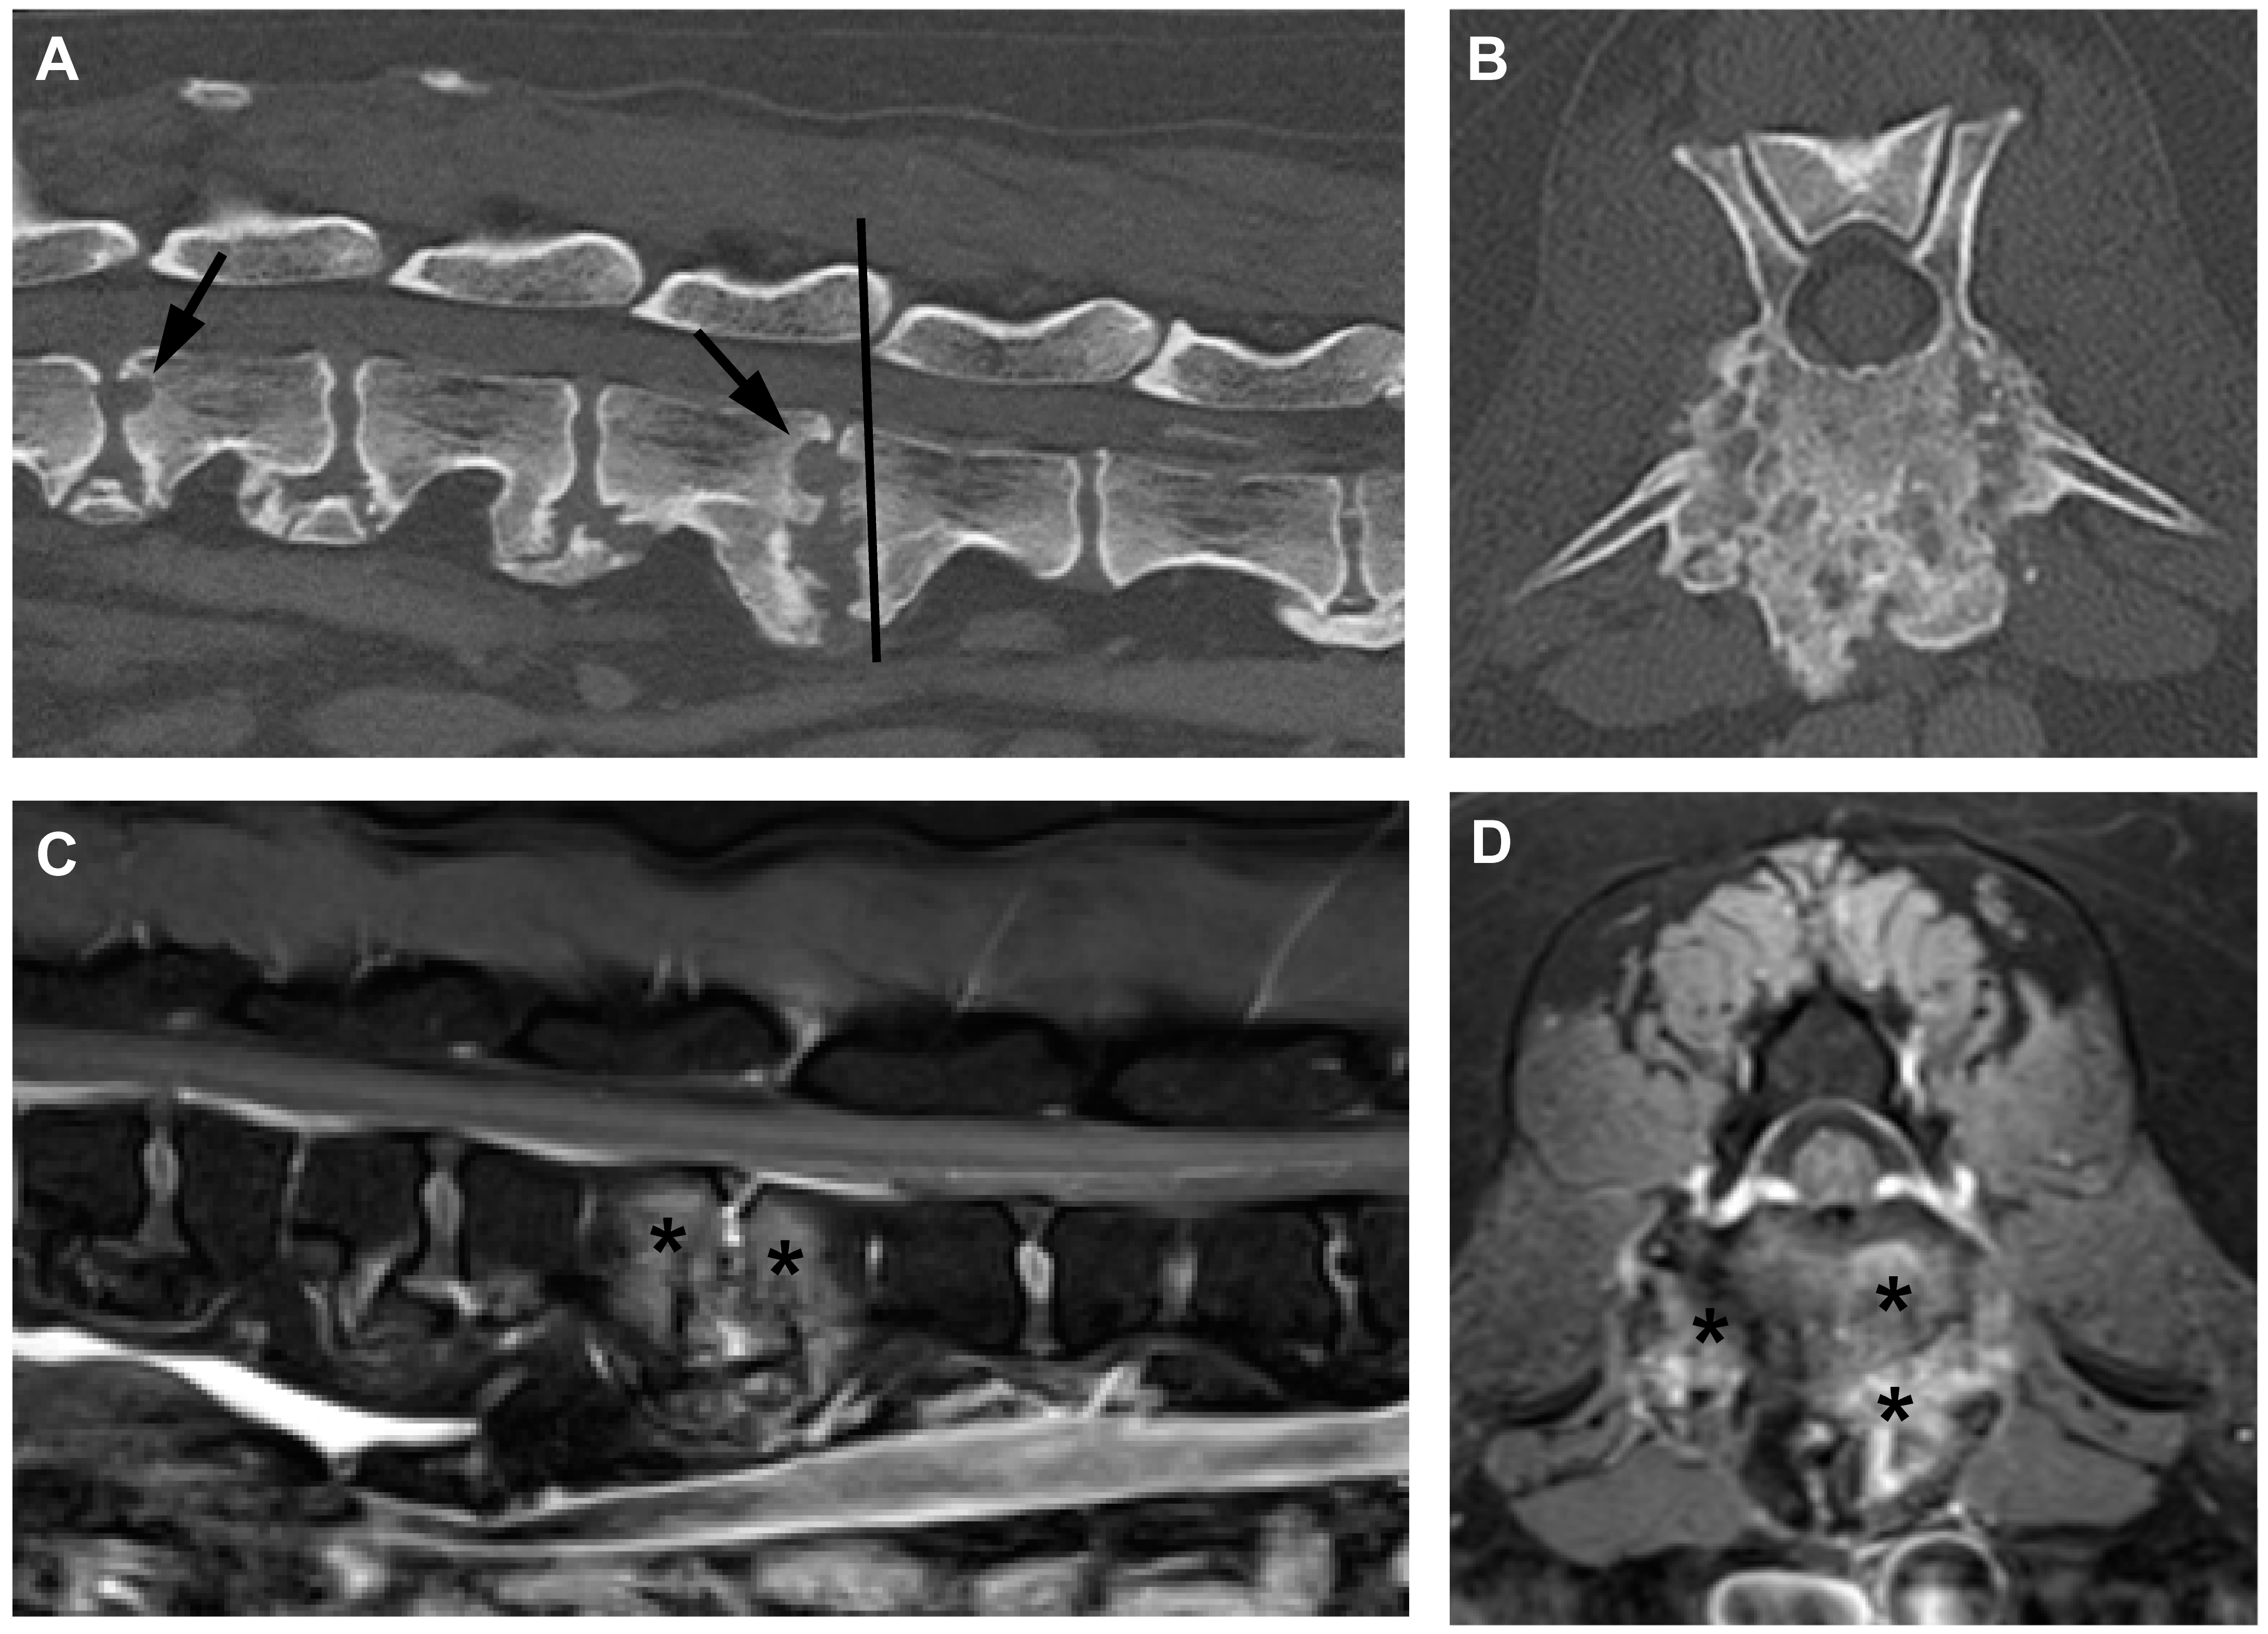

Dogs diagnosed with bacterial infections other than Brucella canis showed a wide variety of lesion appearance (Figure 3); some dogs showed large destructive lesions and some showed more muted erosions with less apparent proliferation and raggedness. Overall, the type of infection was not invariably associated with a specific type of imaging appearance.

Figure 3. Surgically stabilized discospondylitis associated with infection with bacteria other than Brucella spp. (A): mid-sagittal CT image showing subluxation at L2/L3 associated with Pseudomonas discospondylitis in a Great Dane. (B): the lesion was stabilized with a 6-hole 3.5 mm DCP (visible in this dorsal plane CT image) plus a dorsally placed combined pin-and-wire tension band [25]. (C): mid-sagittal CT image showing T3/4 subluxation (arrow) associated with S. canis discospondylitis. (D): in this relatively stable region of the vertebral column the lesion was stabilized using a stacked De Puy CRIF implant [26] with 5 mm clamps and 3.5 mm screws. The stabilized site is indicated by an arrow.